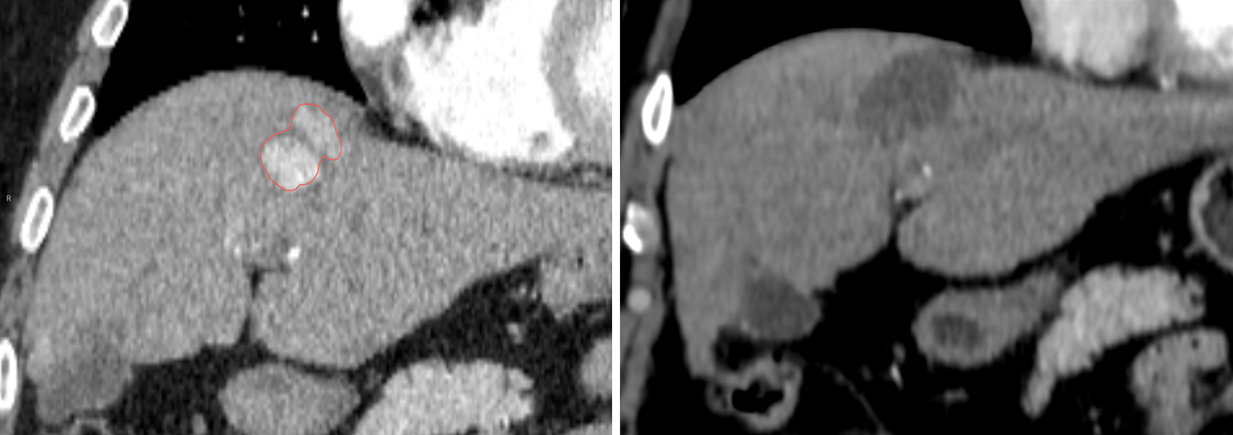

CT Follow-up at 3 months showing complete response

- Follow-up imaging confirmed full coverage of the treated lesion at 3 months and patient was taken off the transplant list due to its good response to the treatment.